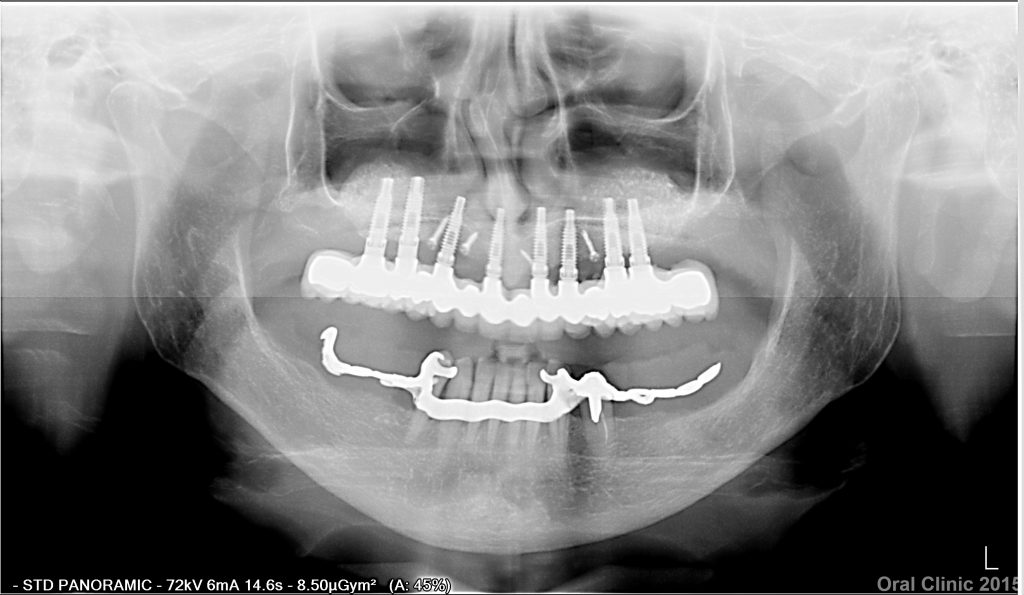

POSE PROTHESE HYBRIDE FIXE TRANSVISEE

Pose d’une prothèse hybride fixe transvissée composite sur 6 implants. Le Docteur Thierry Hascoet vous montre le processus complet d’une pose d’une prothèse hybride fixe transvissée. Il dirige la clinique dentaire de Cunit, (Espagne), Oral Clinic. Plus de 15.000 implants posés.